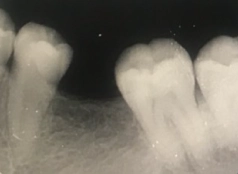

• Tình trạng răng trước đây:Mất răng số R16, R36

Trước đây do chủ quan trong việc ăn uống và chăm sóc răng miệng, anh Trung Tín bị mất 2 răng hàm. Tuy nhiên, anh vẫn để trống vị trí mất răng mà tiến hành không phục hình lại, bởi suy nghĩ vẫn còn những răng khác để ăn nhai.

Cho đến lần kiểm tra răng miệng gần nhất, bác sĩ nhận định xương hàm ở vùng mất răng đã có dấu hiệu tiêu biến và có nguy cơ gây xô lệch những răng chắc khỏe bên cạnh. Do đó, anh Tín bắt đầu tìm hiểu về các phương pháp để khôi phục lại răng mất.